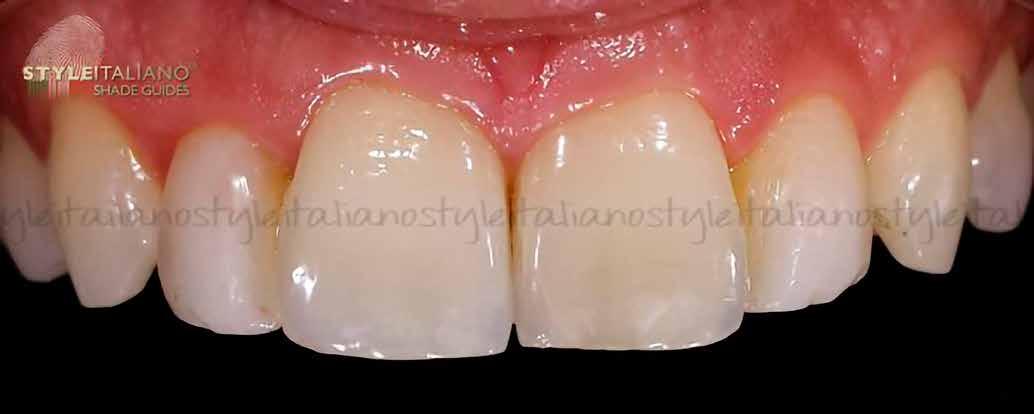

A pácienst 21 nap (14–15. ábrák) és 12 hónap (16. ábra) után ismét ellenőrizzük, hogy értékeljük az esztétikai eredményt a forma és a szín tekintetében.

13. ábra: Az UL1 emulálása polírozás közben. – 14. ábra: A helyreállítás 21 nap után.

15. ábra: A helyreállítás 21 nap után.

16. ábra: A helyreállítás 12 hónap után.